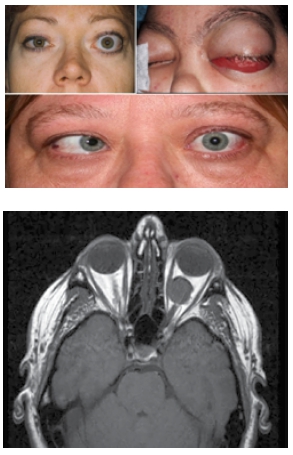

Pacienții care se confruntă cu prezența unei formațiuni tumorale orbitare prezintă adesea exoftalmie (protruzia globului ocular), diplopie (vedere dublă), limitarea mișcărilor globului ocular, scăderea acuității vizuale, edem palpebral, ptoză palpebrală, ochi roșu, durere locală, prezența unei mase tumorale palpabile.